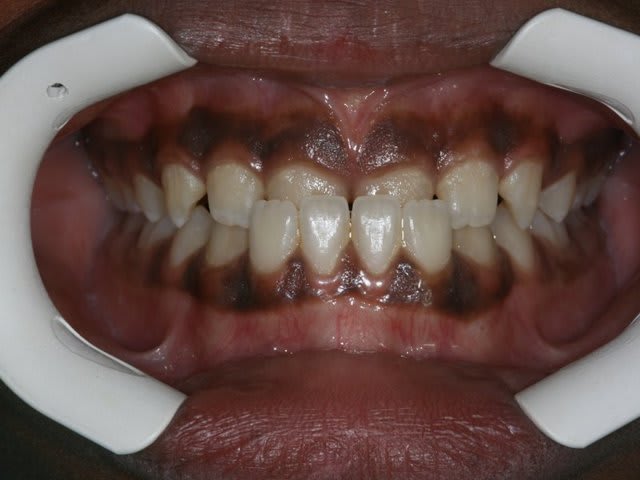

Dam. A.

Age :8 ans

Sexe M.

CL. III.

J’ai demandé à voir les parents, voici les dents du père !!!